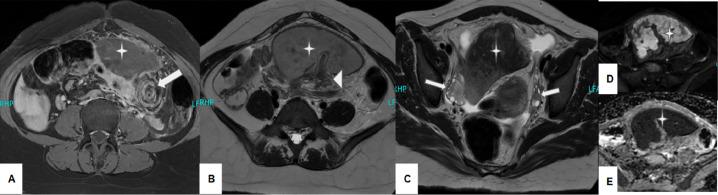

Wandering spleen manifests when the splenic ligaments are underdeveloped, or become lax, thereby allowing the spleen to relocate from its anatomical site to more distant areas. During such movements, torsion of the long splenic peduncle is common, which can lead to symptoms of acute abdomen and further complications such as infarction. It is typically seen in children and young females. Our report presents a case of a 22-year-old female presenting to the ER with complaints of severe pain in the abdominal region. On ultrasound, there was suspicion of an adnexal mass, which was later confirmed to be a misplaced spleen in the lower abdomen, with torsion, fat stranding, and splenic vein thrombosis, as revealed by enhanced CT abdomen and pelvic MRI. It was followed by an emergency splenectomy. As wandering spleen presents nonspecifically and is a rare condition, it is important to consider wandering spleen when patients present similarly to this case, to prevent misdiagnosis and to deliver surgical treatment quickly to preserve the spleen.

游走脾是在脾韧带发育不全或变得松弛时出现,从而使脾脏从其解剖位置移位到更远的区域。在这种移动过程中,脾长蒂扭转很常见,这可导致急腹症症状及进一步的并发症,如梗死。它通常见于儿童和年轻女性。我们的报告介绍了一例22岁女性因腹部剧痛到急诊室就诊的病例。超声检查怀疑有附件包块,后来经腹部增强CT和盆腔MRI证实为下腹部异位脾脏,伴有扭转、脂肪堆积及脾静脉血栓形成。随后进行了急诊脾切除术。由于游走脾表现不具特异性且是一种罕见疾病,当患者出现类似此病例的情况时,考虑游走脾很重要,以防止误诊并迅速进行手术治疗以保留脾脏。